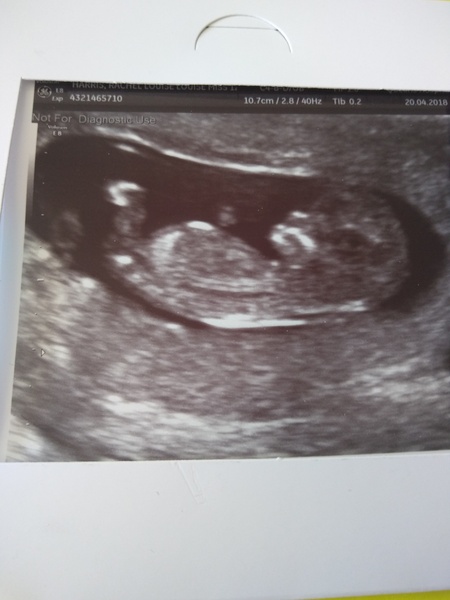

Fireba11 · 20/04/2018 20:52

I had my scan today. My early scan gave me an EDD of 10th Nov but this one said EDD 5th Nov (and should be more accurate) so I've jumped ahead a bit and will apparently be 12 weeks on Monday! I have just stopped feeling nauseous all the time which is a huge plus. Like a lot of you guys I'm now in leggings/maternity jeans and feel as though I look quite pregnant 😳

Scan showed all normal and baby was moving around loads! Just so relieved everything seems to be fine... Long may it continue 😊